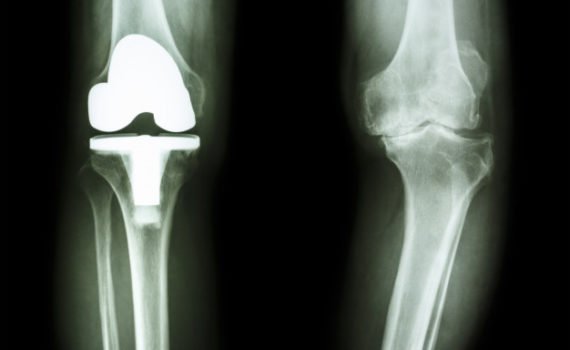

Patologie del Ginocchio. Il ginocchio è un’articolazione che unisce la coscia e la gamba, le quali, insieme al piede, compongono l’arto inferiore. Il ginocchio è composto in realtà da due articolazioni: una tra femore e tibia, e l’altra tra femore e rotula. L’incavo posteriore è chiamato cavità poplitea. Mentre le […]

Dolore al Ginocchio. Il Ginocchio è soggetto a molte patologie. ll dolore al ginocchio può essere causato anche alla degenerazione progressiva della cartilagine del ginocchio dovuta al sovrappeso o a sovraccarico funzionale. Altre condizioni che possono provocare dolore sono la necrosi avascolare, l’emartrosi (reperto classico in caso di emofilia), l’osteomielite […]